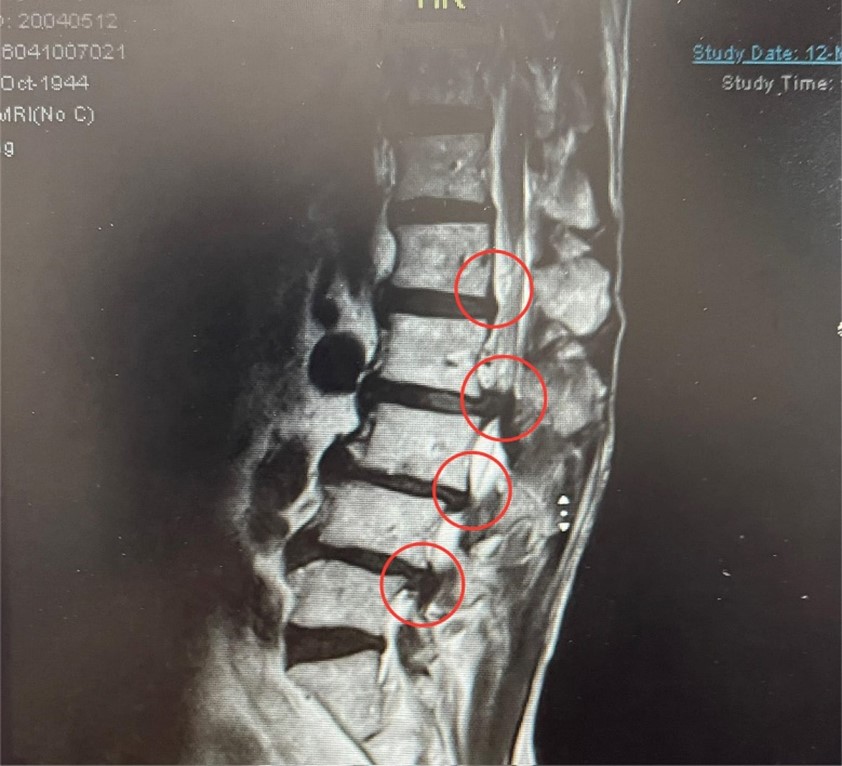

曾先生自 2024 年 3 月起出現臀部至大腿麻痛與外側劇烈疼痛, 檢查發現腰椎 L1–L5 節段不同程度椎間盤突出, 並合併腰椎滑脫。

蔡醫師依據影像檢查與臨床症狀分析, 判斷屬於小針刀適應症, 與患者充分討論後, 規劃分階段治療計畫。